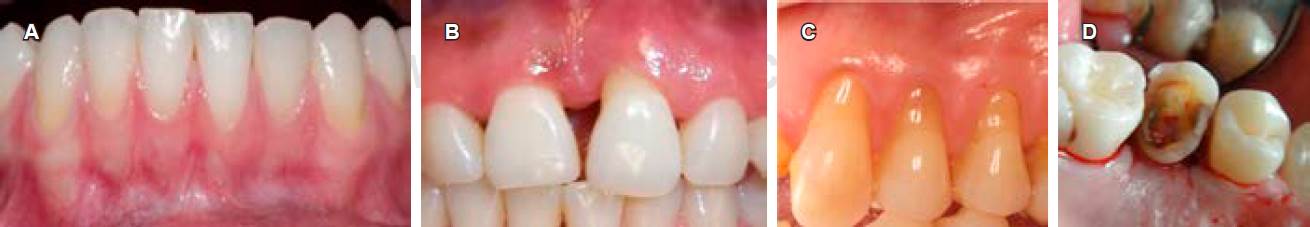

El consenso propone diferenciar entre dos situaciones distintas dentro de la salud periodontal: salud gingival clínica con un periodonto intacto y salud gin gival clínica en presencia de un periodonto reducido (Figura 1).10

La salud gingival clínica en un periodonto intacto es un periodonto estructural y clínicamente sano, esto se refiere a la ausencia de inflamación o de destrucción de los tejidos periodontales (Figura 2A).10

Figura 2 A) Salud gingival clínica en un periodonto intacto. B) Periodonto reducido con periodontitis estable. C) Periodonto reducido sin periodontitis (con recesiones gingivales). D) Periodonto reducido sin periodontitis (por alargamiento de corona).

Paciente con periodontitis estable, cuya periodontitis ha sido tratada exitosamente y los signos clínicos de la enfermedad no parecen agravar la extensión o severidad a pesar de la presencia de un periodonto reducido (Figura 2B).

Paciente sin periodontitis, que presenta un periodonto reducido por recesiones gingivales o que fue sometido a procedimientos resectivos como el alargamiento de la corona (Figuras 2C y 2D).11